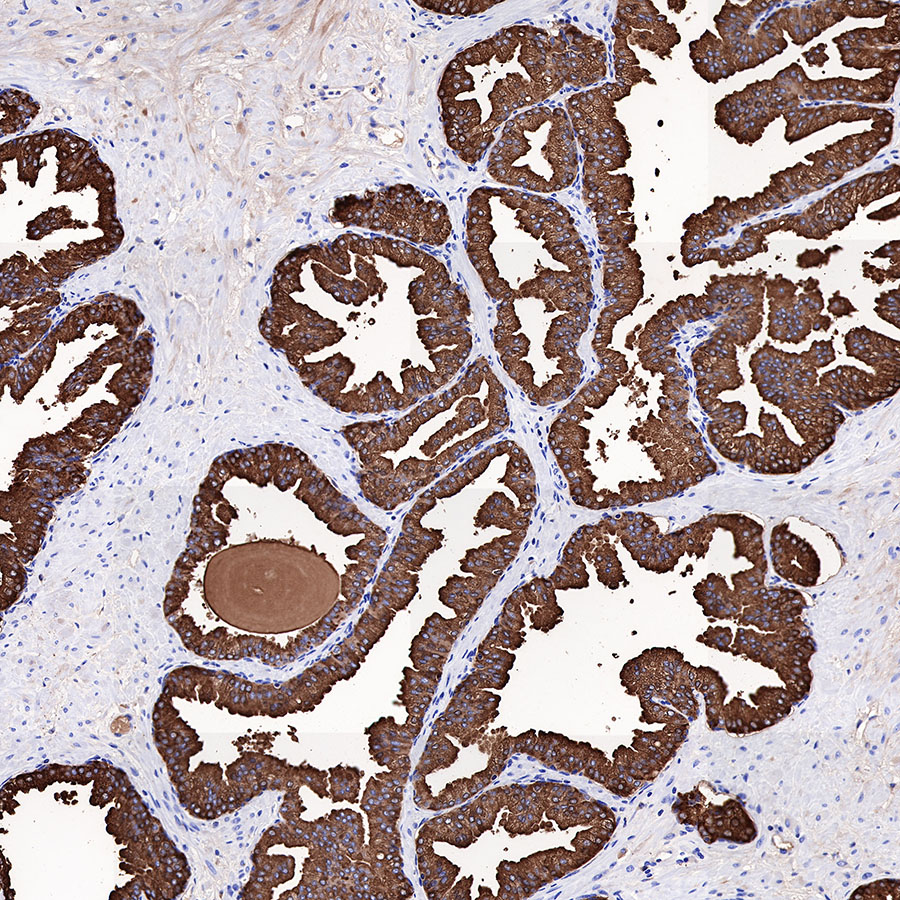

Immunohistochemistry

IHC shows positive staining in paraffin-embedded human prostatic hyperplasia. Anti-PSA antibody was used at 1/1000 dilution, followed by a HRP Polymer for Mouse & Rabbit IgG (ready to use). Counterstained with hematoxylin. Heat mediated antigen retrieval with Tris/EDTA buffer pH9.0 was performed before commencing with IHC staining protocol.